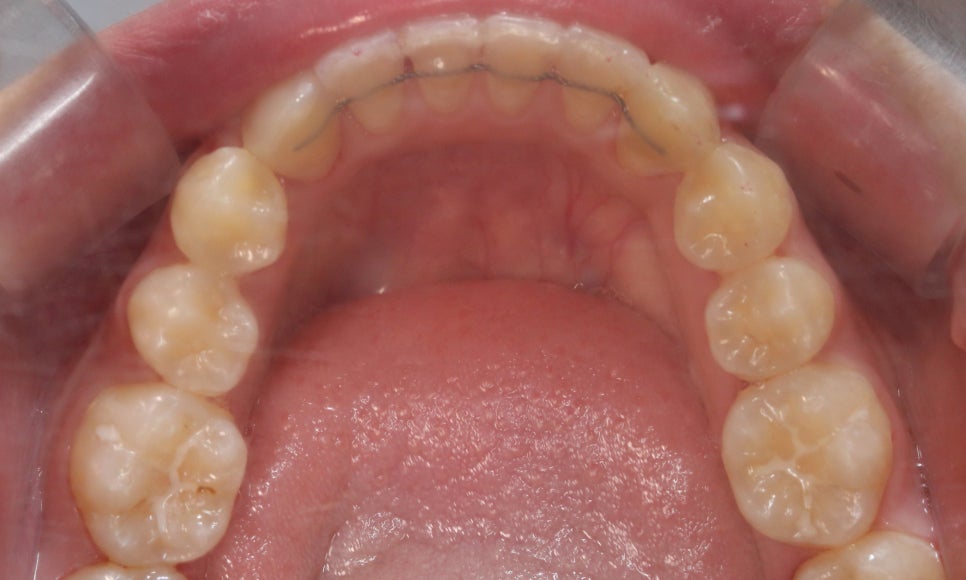

아랫니를 보시면

왜소치가 아님에도 치아 끝이

톱니처럼 울퉁불퉁한 것을 확인할 수 있습니다!

이렇게 왜소치가 원인이 아닌 경우

부정교합으로 인해 치아 끝이 맞물리지 않아

마멜론이 남아있을 수 있을 수 있습니다.

부정교합에 의한 마멜론은

교정치료를 통해 교합 상태를

정상적으로 바꿔주면 자연스럽게

해소될 수 있는데요,

환자분께서도 교정이 끝난 뒤

치아의 끝 모양이 많이 매끄러워진 것을

확인할 수 있습니다~

삐뚤거리던 아랫니 역시

비발치 교정이 끝나고

가지런해진 모습인데요,

이번 환자분께서는

비발치 클리피씨 교정으로

약 19개월의 교정기간이 소요되셨습니다!